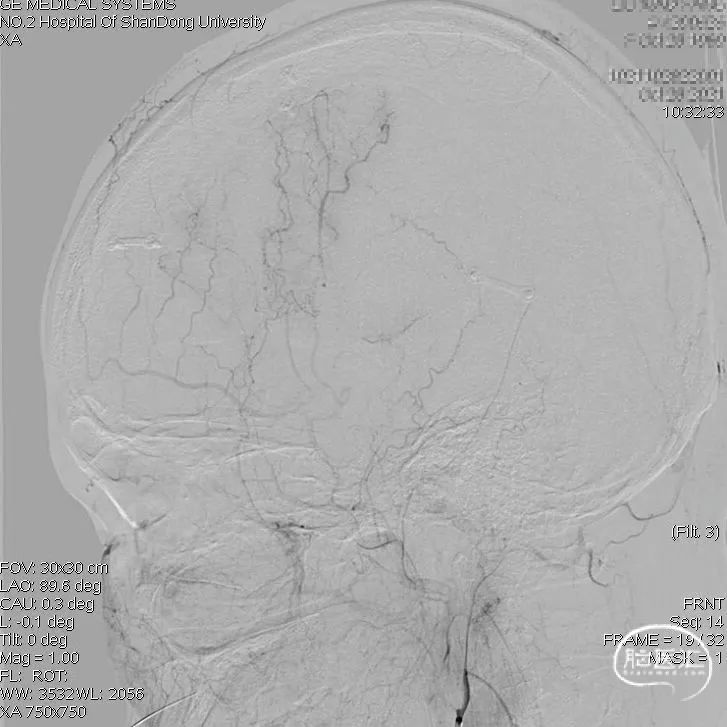

术前右颈内动脉正位:

复查DSA:右侧颈外动脉侧位造影显示桥血管(右侧颞浅动脉顶支)走行向大脑半球上外侧面中央前回区域。

周围还可以看到一些颞浅动脉额支和硬膜新生血管供血。